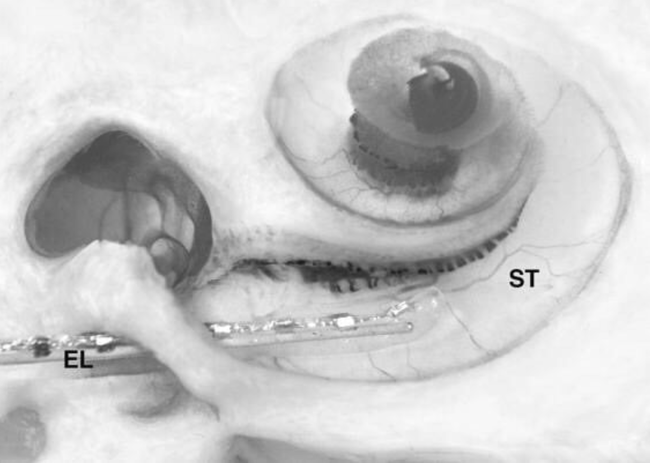

Bệnh nhi là bé gái, nhập viện từ lúc 4 tháng tuổi với bệnh cảnh nghe kém, mống mắt hai bên màu xanh dương ngọc, khóe mắt hai bên cách xa nhau làm che phủ một phần củng mạc trong hốc mắt. Trước trán bé có mảng tóc trắng và mảng bạch biến ở vùng trán, mũi. Rễ mũi bị rộng, điếc hai tai.

Bé gái bị mắt xanh, tai điếc bẩm sinh. (Ảnh: BVCC)

"Bệnh nhân đeo máy trợ thính ba tháng không hiệu quả nên đã cấy ốc tai điện tử để hồi phục chức năng nghe. Tai phải cấy ốc lúc bé 15 tháng tuổi, tai trái cấy sau đó ba năm.

Sau gần 5 năm, bệnh nhi còn nói ngọng nhưng đã có thể nói chuyện qua điện thoại và sinh hoạt, học tập như những đứa trẻ bình thường khác" - bác sĩ Minh chia sẻ.